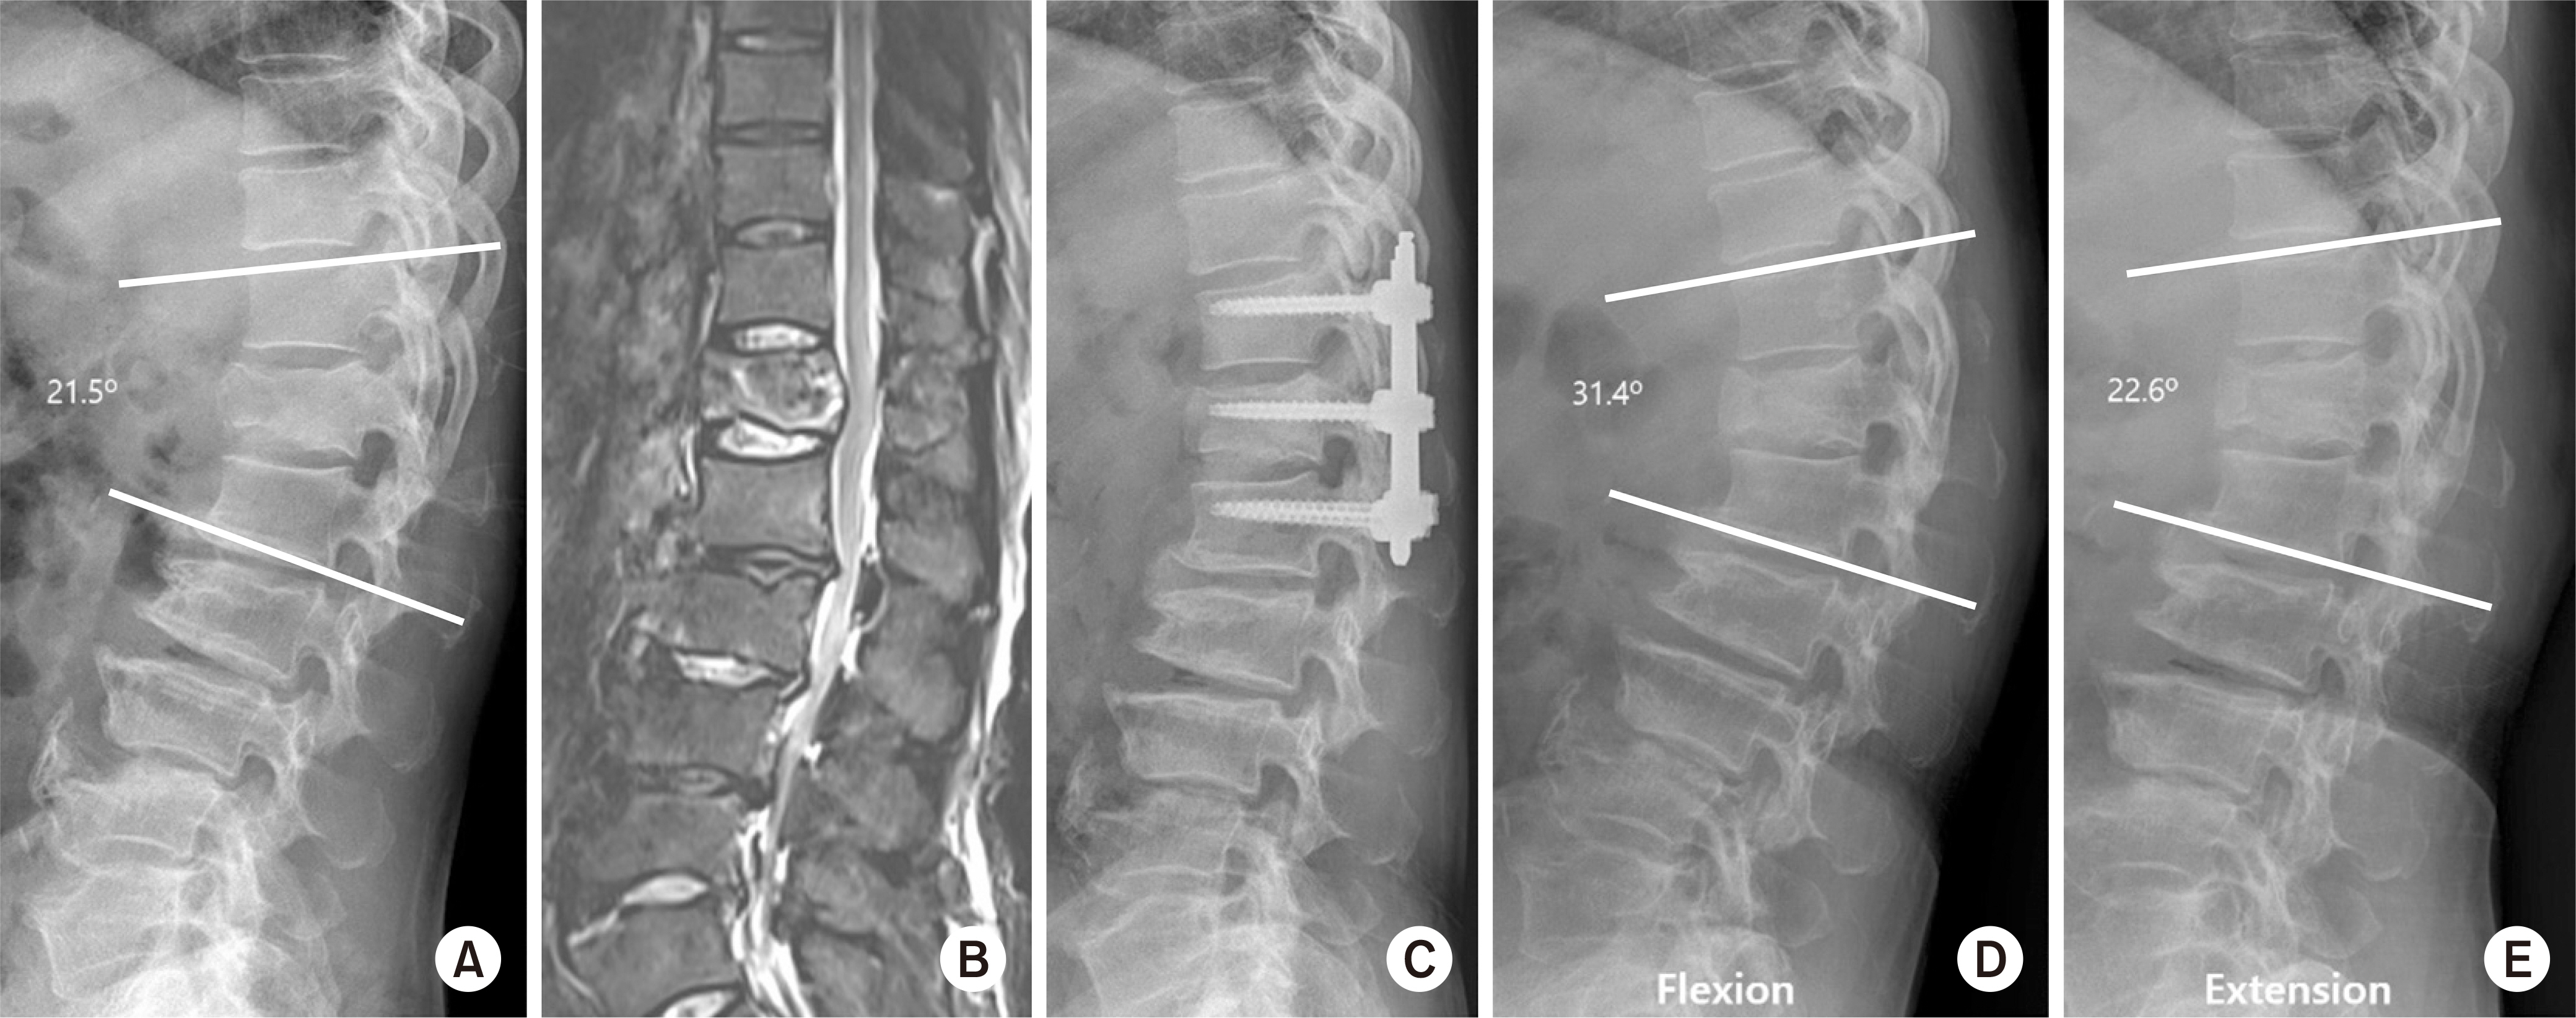

Fig. 3.

A 64-year-old male with flexion-distraction injury on T12. (A) The preoperative lateral X-ray shows fracture of the T12 body and spinous process. (B) On the magnetic resonance imaging (T2 weighted fat suppression), there was acute compression fracture with a spinous process fracture. (C) The lateral radiograph, taken immediately after surgery, shows anatomical reduction. (D, E) Lateral X-ray of the flexion (D)/extension (E) views that show the range of motion of no fusion segment.